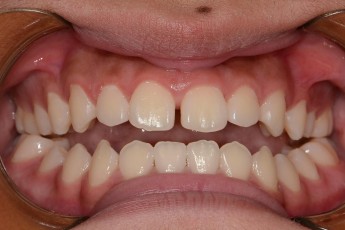

BEFORE & AFTER